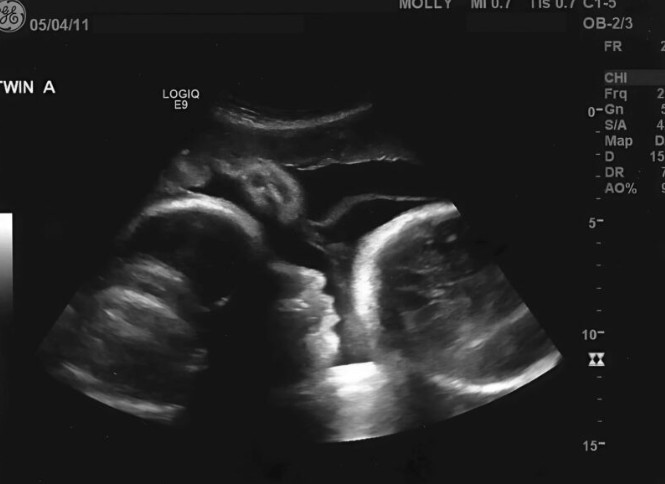

Na kraju, Larisa je odlučila da potraži pomoć, nadajući se da će joj ginekolog potvrditi njene sumnje. Međutim, ono što je saznala bilo je šokantno. Umesto radosne vesti, lekari su otkrili ozbiljan medicinski problem koji je uzrokovao njen rastući stomak. Na ekranu je bilo jasno da nije bilo bebe, već nešto potencijalno opasno što je moglo da ugrozi njeno zdravlje. Osećaj šoka i neverice bio je prisutan, a Larisa je shvatila da je sve vreme verovala u lažnu stvarnost.